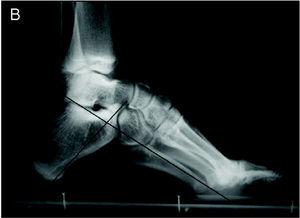

El pie normal es aquel en cuyo fotopodograma A-A' es igual a 2 B-B' (fig. 1). El ángulo de Moreau-Costa-Bartani tiene unos valores de 120-130o y el ángulo astragalocalcáneo (ángulo de Kite) de 15-20o en las proyecciones radiográficas de perfil y dorsoplantar, respectivamente (fig. 2). Los arcos longitudinales del pie van decreciendo progresivamente de 18 a 25o para el primer radio hasta 5o para el quinto radio (fig. 3). En el pie cavo y plano todos estos pará metros están alterados. Aun así, pequeñas alteraciones en estos grados, en ausencia de sintomatología, no pueden considerarse patológicas.

Figura 2. Pie normal: ángulo de Moreau-Costa-Bartani y ángulo astragalocalcáneo.